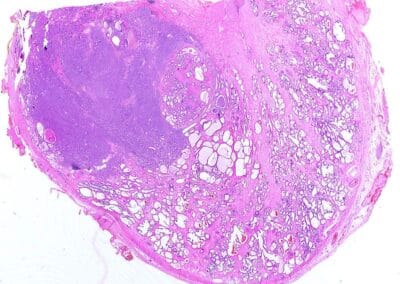

Beurteilung die feingewebsbeschafenheit des Tumors und dessen Aggressivität (3+3=6 nicht aggressiv / 5+5=10 aggressiv).

Die Biopsie der Prostata gehört zur Sicherung der Diagnose. Es werden 12 Proben aus der Prostata MRT- und Ultraschallgesteuert unter Narkose gewonnen und mikroskopisch untersucht. Es nennt sich Fusionsbiopsie der Prostata. Entzündung danach ist sehr unwahrscheinlich. Streuung des Tumours dadurch ist nicht möglich.